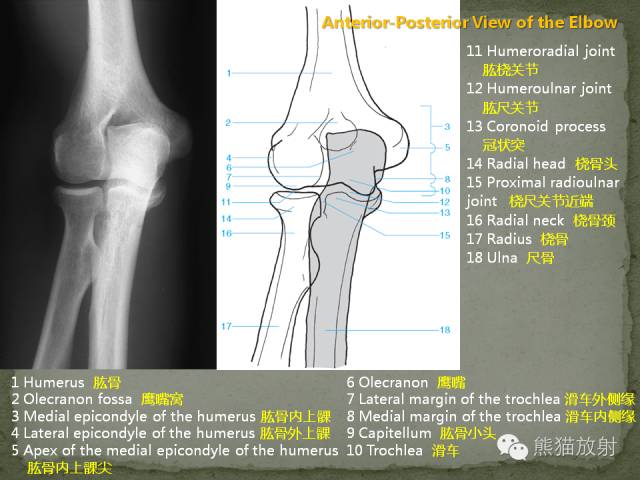

肘关节及前臂X线解剖